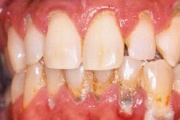

- ige on paistes (mädapunn)

- igemed on tursunud/vohavad (17)

- igemetaskust eritub mäda (3)

- parodontaalne abstsess (2)

- halb hingeõhk / suu haiseb (12)